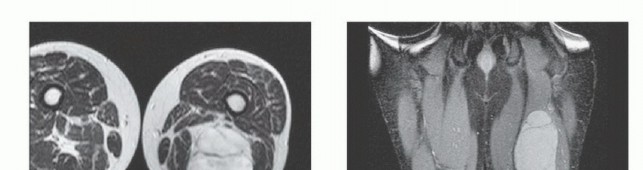

الدراسات التصويرية المتقدمة

تُعد الدراسات التصويرية حجر الزاوية في تشخيص ساركوما الأنسجة الرخوة. تهدف هذه الفحوصات إلى تحديد مدى الورم وعلاقته بالعضلات والعظام والأوعية الدموية والأعصاب، وخاصة العصب الوركي.

- التصوير بالرنين المغناطيسي (MRI): يُعد التصوير بالرنين المغناطيسي الأداة الأكثر فائدة في تقييم ساركوما الفخذ الخلفي. يوفر صورًا مفصلة للأنسجة الرخوة ويساعد في تحديد حجم الورم، وموقعه الدقيق، وعلاقته بالعضلات المحيطة، والعصب الوركي، والأوعية الدموية. كما يساعد في التمييز بين الأورام الحميدة والخبيثة.